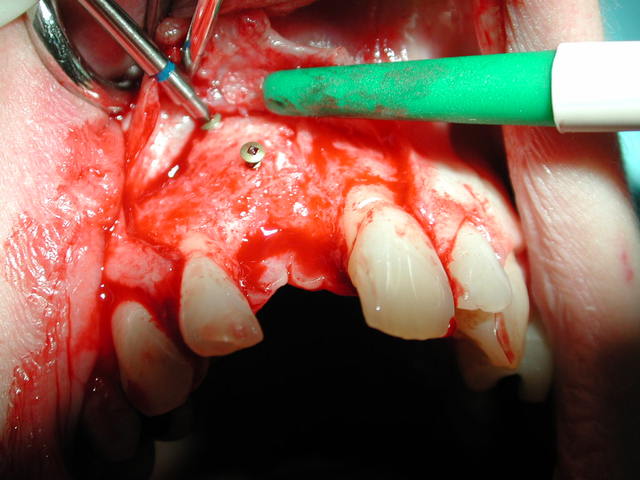

Sur photo 4555 : greffon allogène fixé par 1 ou 2 vis d'ostéosynthèse : immobilisation absolue obligatoire .

Sur photo 4570 : lambeau mucopériosté pour abord de la zone vestibulaire puis épaisseur partielle pour gagner de l'élasticité et recouvrir complètement le surplus de volume causé par le greffon + les membranes de PRF qui protègent ce greffon.

Sur photo 1401 : autre patient lors de la réouverture à 6 mois : l'os allogène est rescussité : n'ayons pas peur des mots !!!

Sur photo 1411 : le greffon est parfaitement intégré et le forage ne sépare pas le greffon de l'os nourricier palatin ; ce qui était ma petite angoisse la première fois que j'ai fait çà .